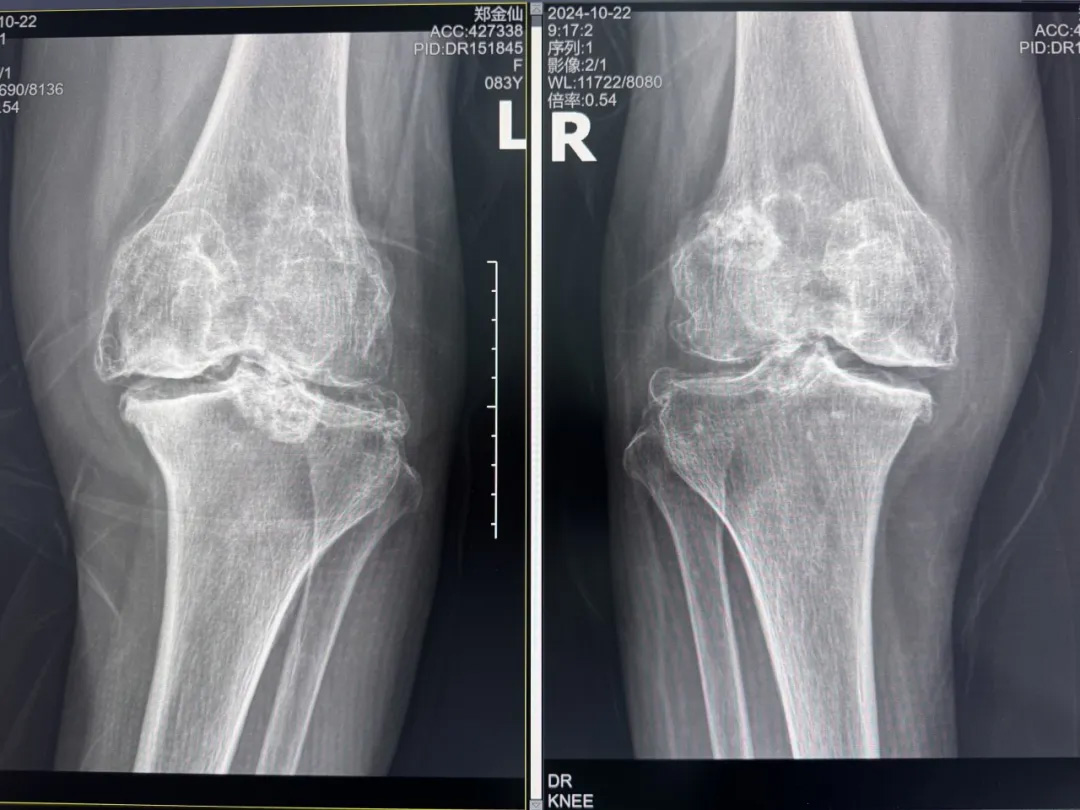

年輕時(shí)愛(ài)到處走走的鄭阿婆,晚年卻被雙膝劇痛困在輪椅上長(zhǎng)達(dá)二十年。經(jīng)羅副院長(zhǎng)診斷,她的膝關(guān)節(jié)軟骨幾乎磨光,關(guān)節(jié)嚴(yán)重畸形,呈"羅圈腿",走幾步便疼痛鉆心,連如廁都需家人抱扶。“我這輩子啊,估計(jì)再也站不起來(lái)了。”是阿婆最常說(shuō)的話。